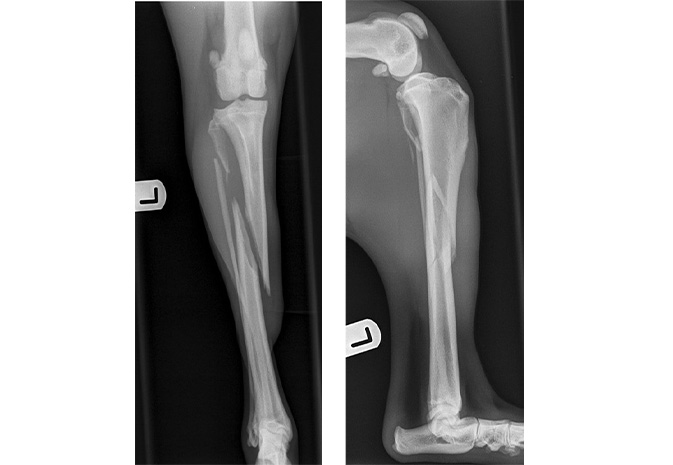

Denzyl presented as an emergency after he had been playing, jumped, cried out and suddenly was unable to weight bear on his left hind limb. On examination, his tibia palpated as crepitant, with large amounts of swelling. He was administered pain relief and sedated for radiography. Images showed unstable oblique fracture of the tibia and fibula.

Oblique fracture of the left tibia and fibula